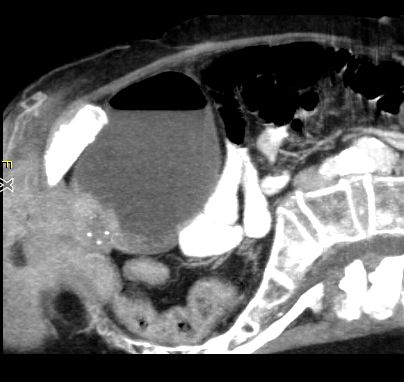

Scheidenende |

75-jährige Frau, bei der vor 3 Jahren ein Vaginalkarzinom exzidiert und bestrahlt wurde. Vor einem Jahr Endometriumkarzinom FIGO IB, G2, OP ohne Nachbehandlung. Jetzt Rezidiv des Endometriumkarzinoms am Scheidenende.![]() | ||